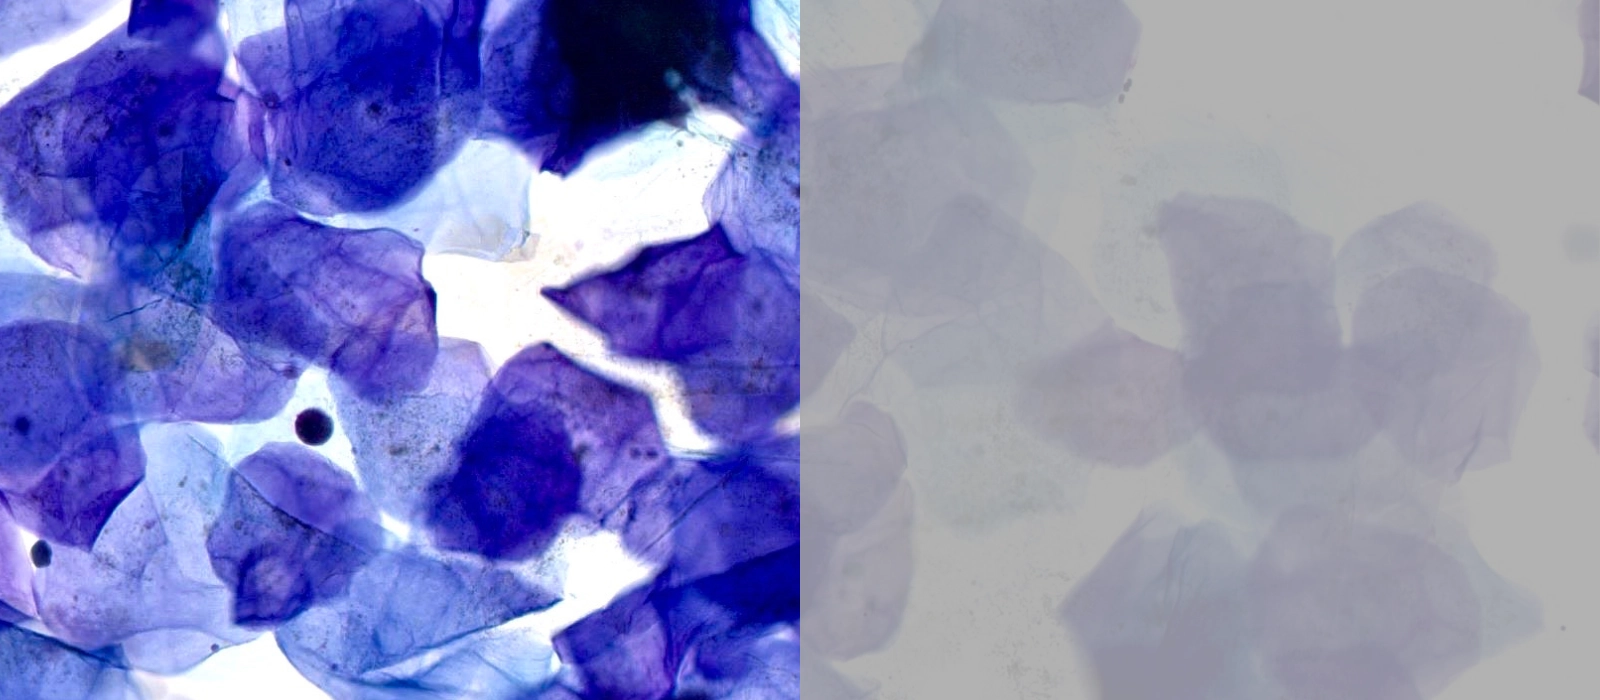

Iedere patiënt verdient de beste behandeling en die begint bij de juiste diagnose. Voor het stellen van de juiste diagnose is inzicht in de voorgeschiedenis van de patient van eerder cel- en weefselonderzoek een grote toegevoegde waarde. De data hiervan moeten veilig en gestructureerd worden opgeslagen en beschikbaar zijn voor de behandelende patholoog. Op deze manier kan de patholoog met volledige inzicht vanuit de pathologie, informatie bijdragen aan het behandelteam.